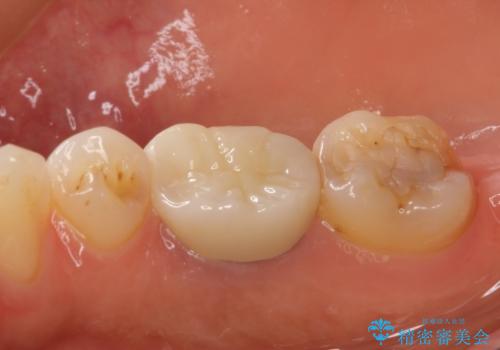

フルジルコニアクラウンを装着してからは、気になっていた金属の縁がなくなり、また、咬み合わせも非常に安定しており、患者様には大変満足していただきました。